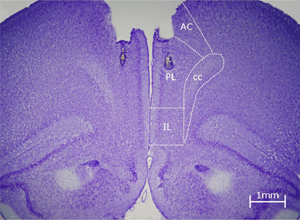

En este trabajo se quiso determinar si una región de la corteza prefrontal, que recibe acetilcolina del núcleo basal magnocelular, podría participar en el aprendizaje de transmisión social de preferencia alimentaria. Para tal fin, se inyectó en la corteza prefrontal prelímbica una substancia llamada escopolamina, que bloquea un tipo de receptores de la cetilcolina. Los resultados indicaron que la infusión de escopolamina antes de la interacción social dificulta la expresión de la preferencia alimentaria (escoger comida con olor de canela en este caso). Estos efectos no fueron debidos a problemas olfativos, de motivación o de falta de interacción social.  Esta investigación sugiere que la corteza prefrontal prelímbica utiliza la modulación colinérgica para operaciones cognitivas como la flexibilidad conductual, la atención o la planificación estratégica, que pueden ser necesarias para la correcta expresión de la transmisión social de preferencia alimentaria.

Escorça prelímbica.